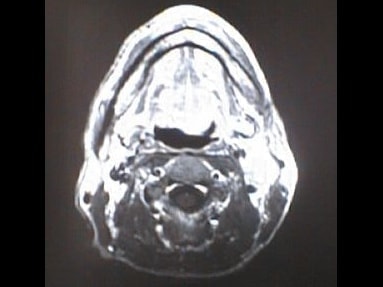

中咽頭末期がんMRI画像②

入院当時MRI画像②

中咽頭末期がん消滅時MRI画像②

入院3か月後癌消滅MRI画像②

中咽頭末期がんMRI画像③

入院当時MRI画像③

中咽頭末期がん消滅時MRI画像③

入院3か月後癌消滅MRI画像③

中咽頭末期がんMRI画像④

入院当時MRI画像④

中咽頭末期がん消滅時MRI画像④

入院3か月後癌消滅MRI画像④